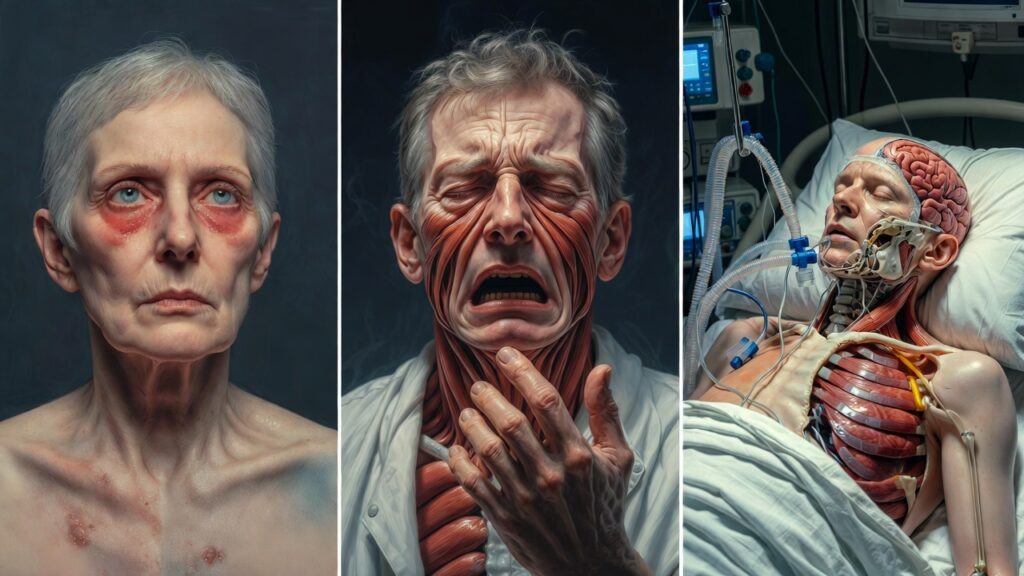

Early Symptoms

Initial symptoms are often nonspecific and resemble common viral illnesses, which can delay diagnosis:

- Fever

- Headache

- Myalgia

- Fatigue

- Nausea and vomiting

Progressive Symptoms

Patients may develop the following as the disease progresses:

- Persistent cough

- Shortness of breath

- Sore throat

- Dizziness

- Altered mental status

Severe and Life-Threatening Symptoms

In severe cases, Nipah virus causes:

- Acute encephalitis

- Seizures

- Loss of consciousness

- Coma

- Acute respiratory failure

Neuropsychiatric Manifestations

The Nipah virus is particularly troubling from a neurological and psychiatric point of view. In my clinical perspective, patients may exhibit:

• Acute delirium and confusion

• Behavior deprivation

• Anxiety and agitation

• Hallucinations

• Personality development

These symptoms emphasize the virus’s direct brain involvement and emphasize the need for multidisciplinary care.

Neurological Sequelae in Survivors

Survivors may suffer from long-term complications, including:

- Persistent cognitive impairment

- Memory deficits

- Speech and motor difficulties

- Seizure disorders

- Chronic fatigue

Psychiatric and Psychological Impact

Although prevalent, post-infection psychiatric disorders are frequently overlooked:

• Irritation

• Anxiety disorders

• Post-traumatic stress disorder (PTSD)

• Social withdrawal

These conditions have a significant impact on quality of life and necessitate ongoing mental health care.